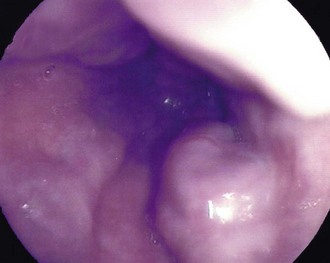

Dysphagia or pain on swallowing (odynophagia) in a middle-aged or elderly patient demands urgent investigation to exclude carcinoma (see Box 22.1). General physical examination is usually unrewarding except in advanced disease. In these cases, there may be signs of wasting, hepatomegaly due to metastases, a Virchow's node in the left supraclavicular fossa or sometimes hoarseness from recurrent laryngeal nerve involvement. Gastroscopy allows direct inspection of the oesophagus using a flexible endoscope and biopsies are taken of any suspicious areas (Fig. 22.2).

Chest X-ray may show the mediastinal shadow is widened by a dilated oesophagus; sometimes a fluid level in the oesophagus is visible behind the heart Fig. 22.7(b). At endoscopy the typical appearance is of a capacious distal oesophagus, usually with food and fluid residue, and a tight lower oesophageal sphincter that may or may not admit the tip of the gastroscope. It is important to see the oesophago-gastric junction to exclude an occult neoplasm masquerading as achalasia (pseudoachalasia). Barium swallow examination reveals gross dilatation of the oesophagus with a tapering constriction (often described as a ‘bird’s beak’ or ‘rat’s tail’) at the lower end. The constriction barely allows contrast to enter the stomach (see Fig. 22.8). Under fluoroscopic screening, uncoordinated purposeless peristaltic waves can often be seen; these are described as tertiary contractions, distinct from normal coordinated primary and secondary contractions. Oesophageal manometry is the cardinal test for achalasia, demonstrating excessive lower oesophageal sphincter pressure that fails to relax on swallowing, and abnormal peristalsis in patients with a more chronic history.

The condition is by its nature incurable, and treatment aims to relieve the distal obstruction. The standard operation is a laparoscopic abdominal procedure involving a longitudinal incision of the lower oesophageal and upper gastric muscle wall until the mucosa bulges through (Heller's cardiomyotomy); this is best combined with a partial fundoplication to overcome the almost inevitable reflux it will cause. Balloon dilatation is sometimes used as an alternative but often needs to be repeated. Botulinum toxin (Botox) is now often used to relax the lower oesophageal sphincter and is an excellent temporising measure, but needs to be repeated after 3–6 months as the effect wears off. Patients with achalasia should be followed up and periodically endoscoped to exclude developing squamous carcinoma (see Fig. 22.9).